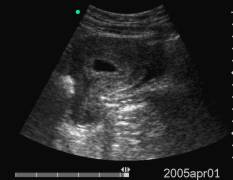

Data inserimento: 15 /07/2005Data esame: 28/06/2005 Strumento: Toshiba 380A Età paziente: F 40 anni Gravidanza alla V settimana di gestazione, documentata per via sovrapubica e per via transvaginale, con evidenza in ambedue le modalità della camera gestazionale. Elaborazione digitale: Andrea Dini